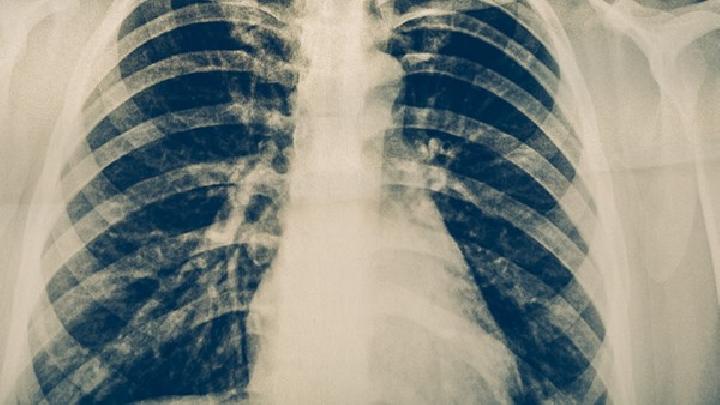

虽然一般干燥综合症不会使病人死亡,但是如果没有进行积极有效的治疗,会加重病情的发展,导致其他脏器的损伤。病人会因唾液分泌的缺乏,导致口干、舌裂、咀嚼困难。也会出现口臭、龋齿、牙龈萎缩。病人的汗腺分泌减少、甚至无汗。女性会出现阴道干燥、外阴萎缩。还会因泪腺功能障碍而导致泪液分泌减少,会造成眼干,出现烧灼感,严重的话会引起眼结膜、角膜感染及溃疡,甚至引起葡萄膜炎、青光眼等严重的眼科疾病。也会出现轻度、自限性关节疼痛、血管炎、肺纤维化等病症。